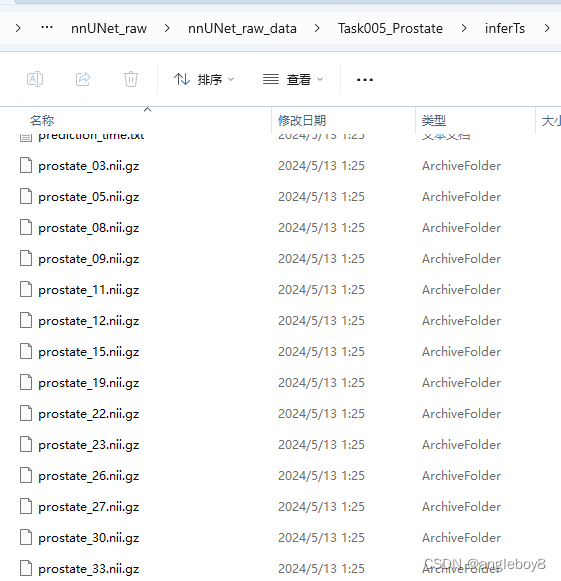

以imagesTs为例:

nnUNet_predict -i 自己的路径\nnUNet_raw\nnUNet_raw_data\Task005_Prostate\imagesTs -o 自己的路径\nnUNet_raw\nnUNet_raw_data\Task005_Prostate\inferTs -t 5 -m 3d_fullres -f 0运行结果:

推理后得到标注结果: